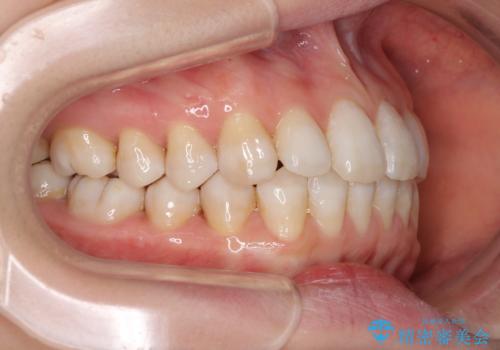

話しにくいオープンバイト インビザラインによる矯正治療

- 前歯の上下スペースによる話しにくさを気にして来院された患者様です。

インビザラインにより上下の前歯の隙間を閉じていくこととしました。

上下の奥歯を圧下させるようにすることで、前歯を接触させるように計画しました。

隙間に舌が入り込むことが話しにくさに繋がっていたため、舌の筋肉のトレーニングも並行して行い、話しにくさの改善と後戻りの抑制を図りました。